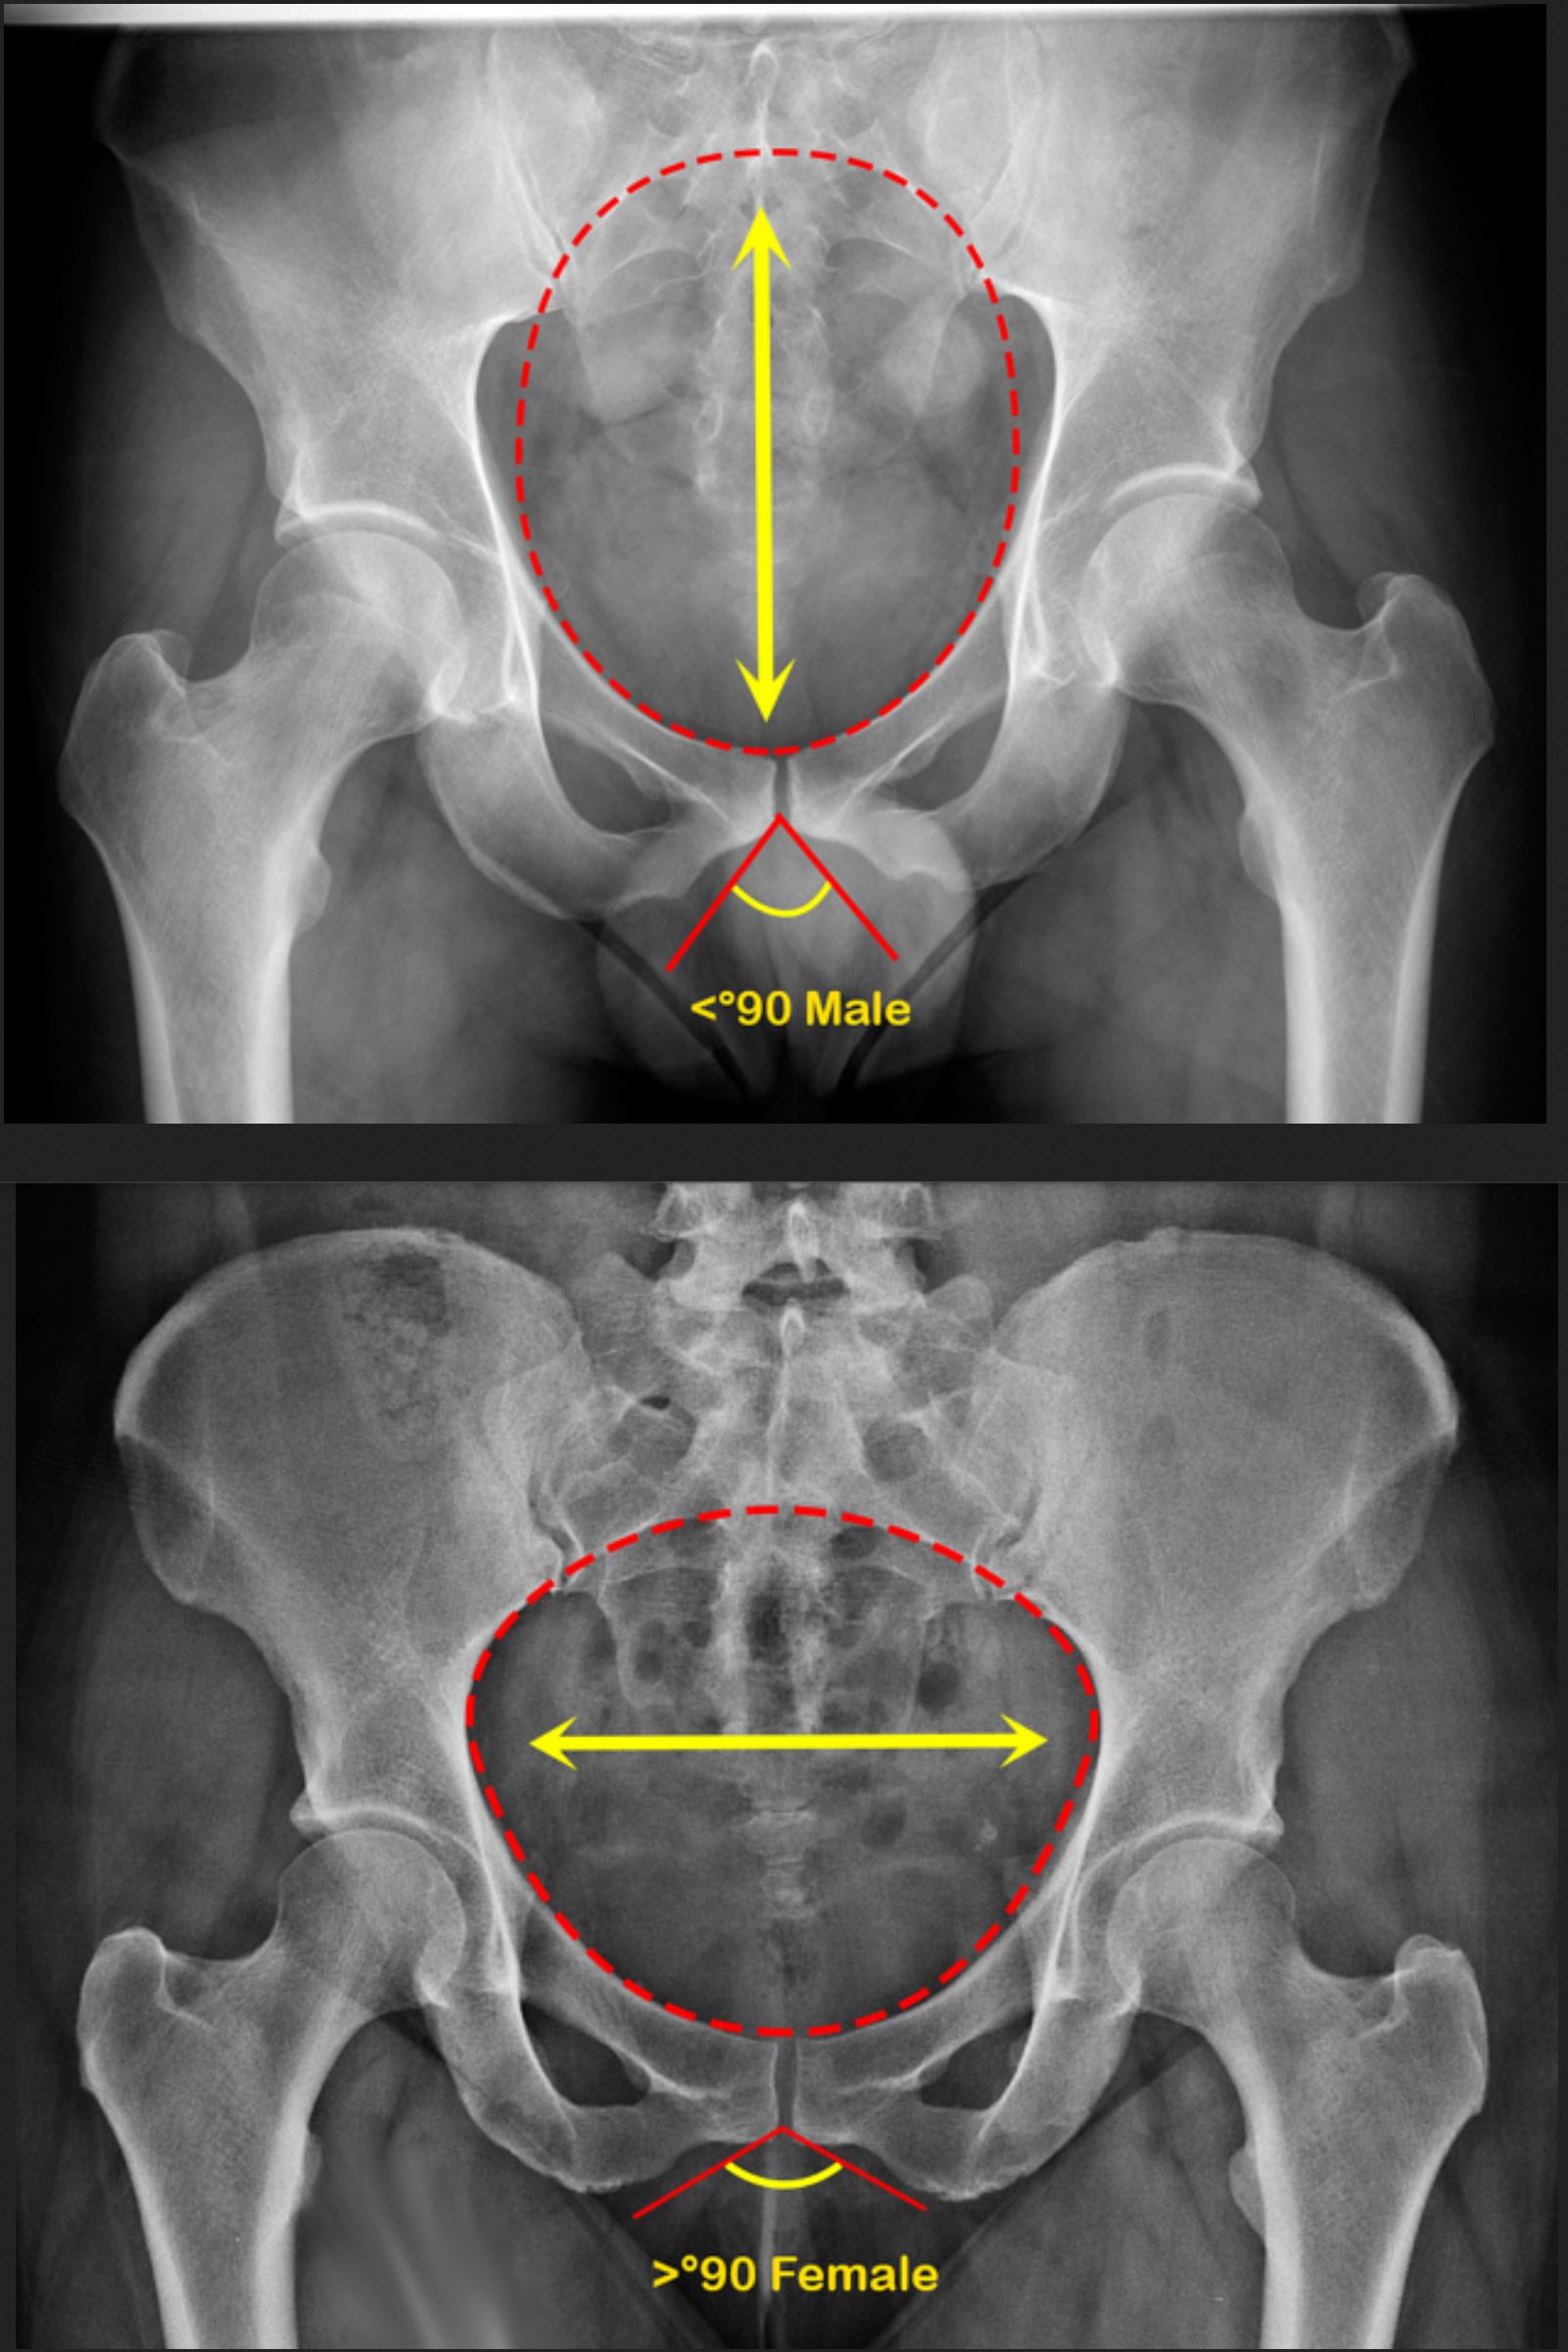

We're going to get to the point where some jew evil doctor is transplanting wombs into men but they still can't give birth because their bone structure is literally not meant for it.